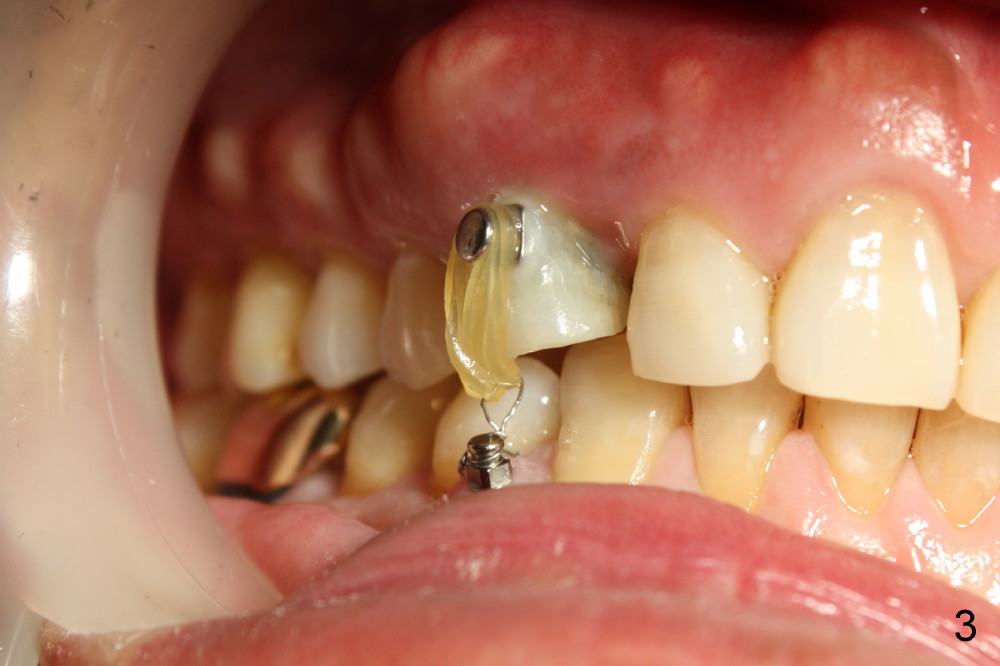

A 1.6x6 mm mini-implant was placed between #27 and 28 on 02/20/2014 (Fig.1,2). The major problem is its angulation. A 1/4 elastic cannot be placed over it. Instead a ligature wire is used to hold the elastic in place (Fig.3,4, taken 2 months later). Occlusal reduction is done (Fig.4), which alleviates the discomfort. But the extrusion is not obvious, since retraction is not 24 hours. The elastic and wire needs replacement quite often, which is not patient friendly. The extraoral Bitewing is taken 2.5 months post implantation (Fig.5). The tooth #6 has a long root. What should we do?